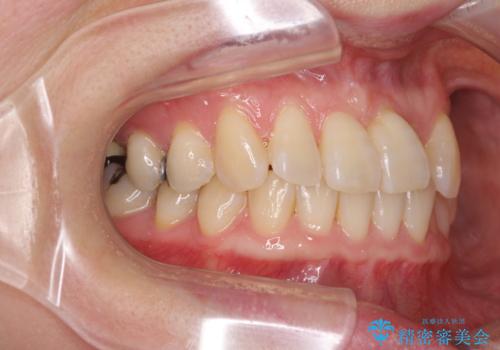

前歯のクロスバイト インビザライン矯正で改善

- むし歯治療を契機に、長年気にしていた前歯のクロスバイトの改善を希望された患者様です。

汚れが溜まりやすく、歯ぎしりがうまくできないため、インビザラインを用いて矯正治療を行うこととしました。

インビザラインによる前歯のクロスバイトの改善は、治療期間中に前歯でしか咬めない時期が続いたり、歯肉退縮や歯髄壊死のリスクが高まったりと、治療中にトラブルを抱えることがあります。

特に上顎側切歯(真ん中から2番目の歯)が舌側に引っ込んでいるケースは、インビザラインでは改善しきれないことがあると言われています。